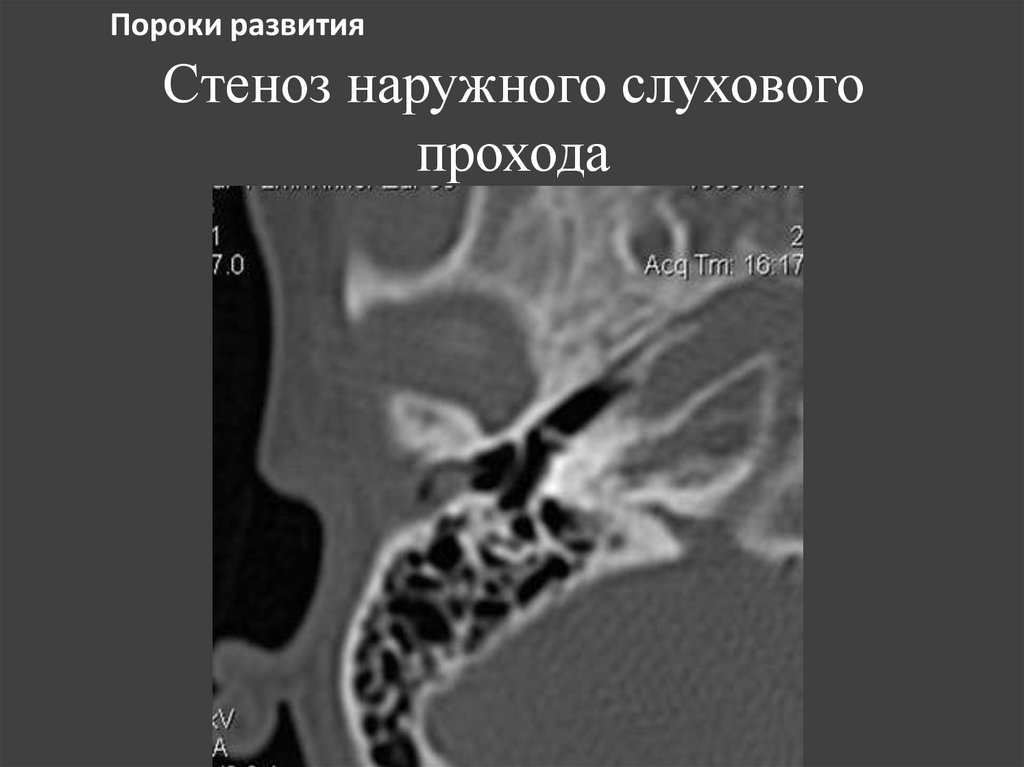

152. Стеноз наружного слухового прохода

Пороки развития

Стеноз наружного слухового

прохода

153. Стеноз НСП